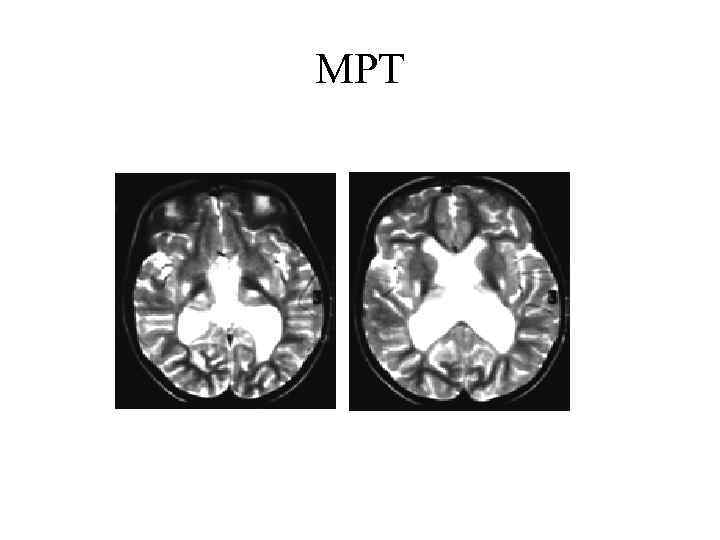

МРТ проводится по показаниям (для исключения врожденных аномалий ликворной системы и других форм церебральных дисгенезий).

МРТ